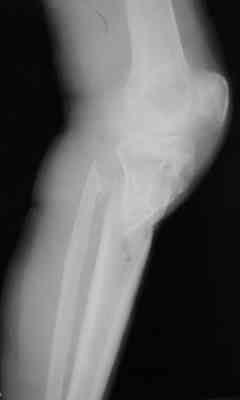

Re: Очередная "проблемная" голень - ложный сустав

Р-граммы за март и апрель